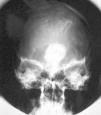

Una variante histológica poco frecuente, descrita en prolactinomas44, somatotropinomas45-47 y adenomas mixtos productores de GH y prolactina48, es la calcificación completa del tejido neoplásico, conocida comúnmente como piedra hipofisaria (figs. 3-5). Esta calcificación se ha relacionado en algunos prolactinomas con la presencia de depósitos de ácido hialurónico y condroitín-sulfato48, mientras que otros autores apuestan por una calcificación metastásica del tejido y la cápsula tumoral47. Estos adenomas productores de GH se han relacionado con un curso evolutivo lento47.

Fig. 3. Radiografía simple, anteroposterior de cráneo en una pa-ciente con adenoma mixto calcificado productor de GH y prolacti-na (piedra hipofisaria)48. (Con permiso de la revista Medicina Clínica, Ediciones Doyma, S.L.)